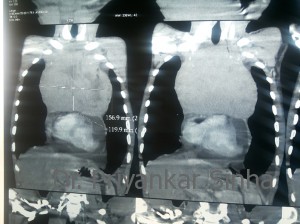

CT scan showing the mediastinal tumor